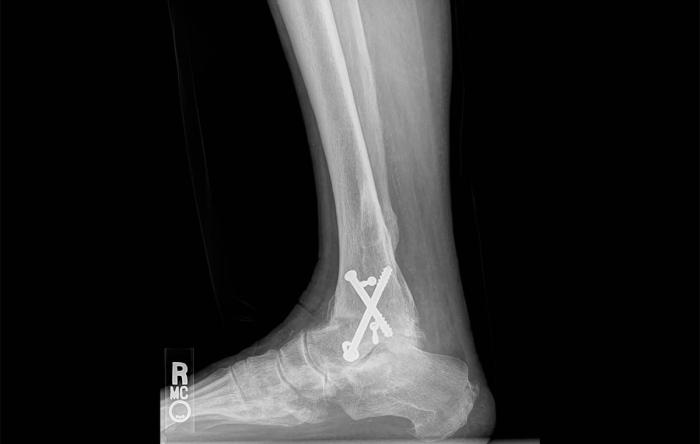

How Do You Know If Your ACL Surgery Failed?

ACL surgery is performed more than 100,000 times...